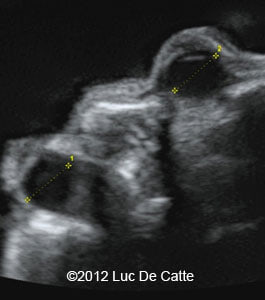

Image 3, 4: Single umbilical artery and ocular hypertelorism

screenshot_159

screenshot_158

• Ocular hypertelorism

• Single umbilical artery